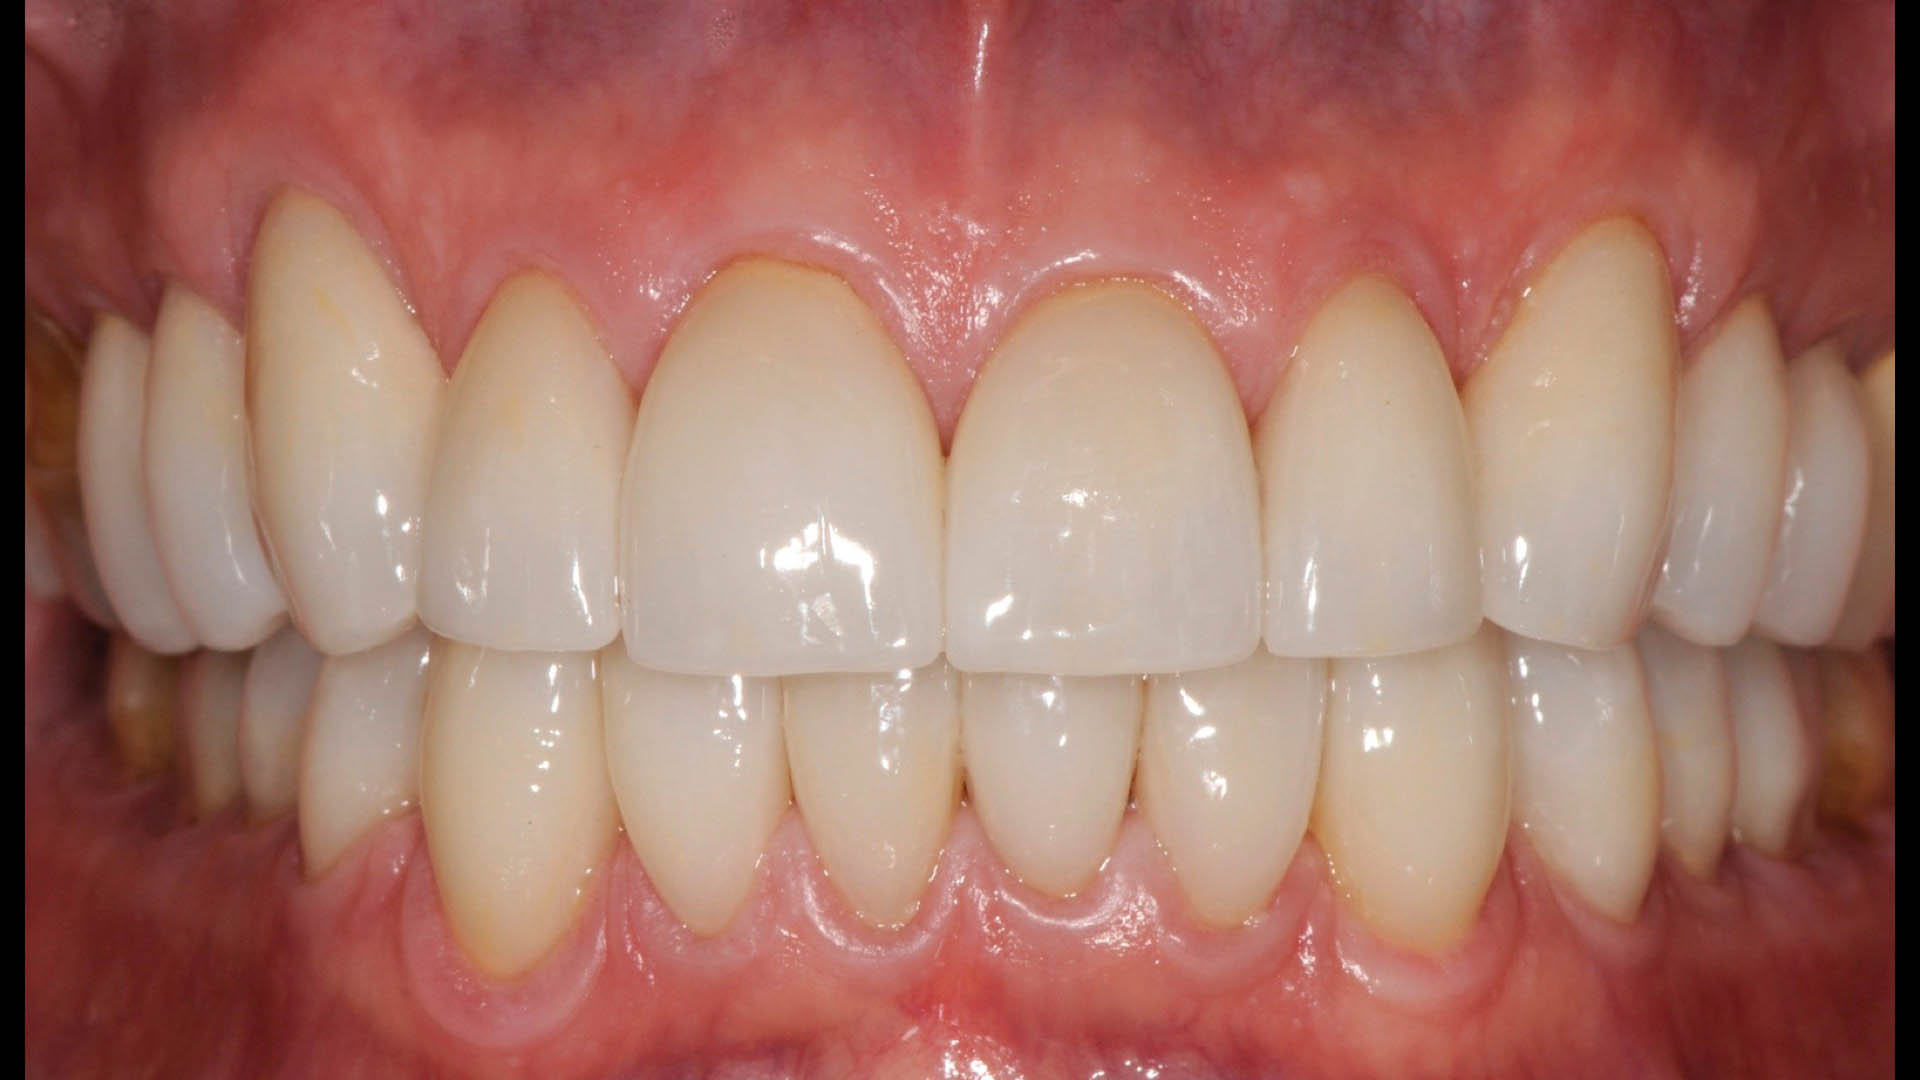

Take a glimpse into the magic of Coral Gables Dentistry through our before and after pictures. See firsthand the incredible smile makeover transformations that have brought confidence and joy to our patients.